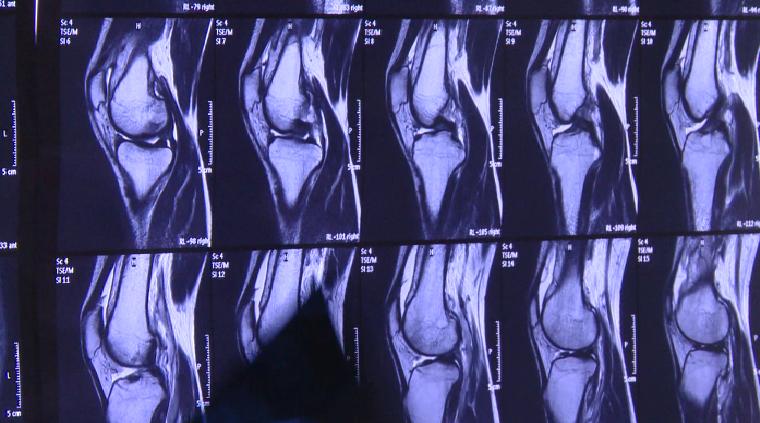

去到医院一检查,医生告诉黄大爷,他患上了膝关节滑膜炎和骨刺,而且这病完全就是“走出来”的。

专家表示,随着年龄地增长,骨关节会产生退行性变化,这是自然现象,但因此完全停止运动或者过量运动都是错误的。中老年人可以选择一些温和的运动,比如匀速骑自行车运动、游泳等。

【国家体育总局运动医学研究所体育医院运动创伤科主任 周敬滨:如果膝关节有症状,或者膝关节疼痛的话,有几个运动就少做了,第一个是爬山运动,第二个是像羽毛球运动,第三种像太极拳运动,这种半蹲位的动作都是对膝关节压力非常大的动作。】